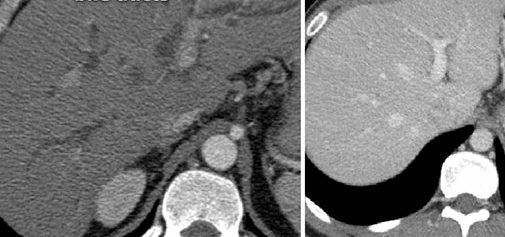

КТ в разных проекциях показывает опухоль в левой почке (стрелка)

Органы брюшной полости, ретроперитонеального пространства. КТ живота является точным методом для диагностики абдоминальных патологий:

опухолей (КТ показывает стадию и распространенность рака, ответ на лечение).